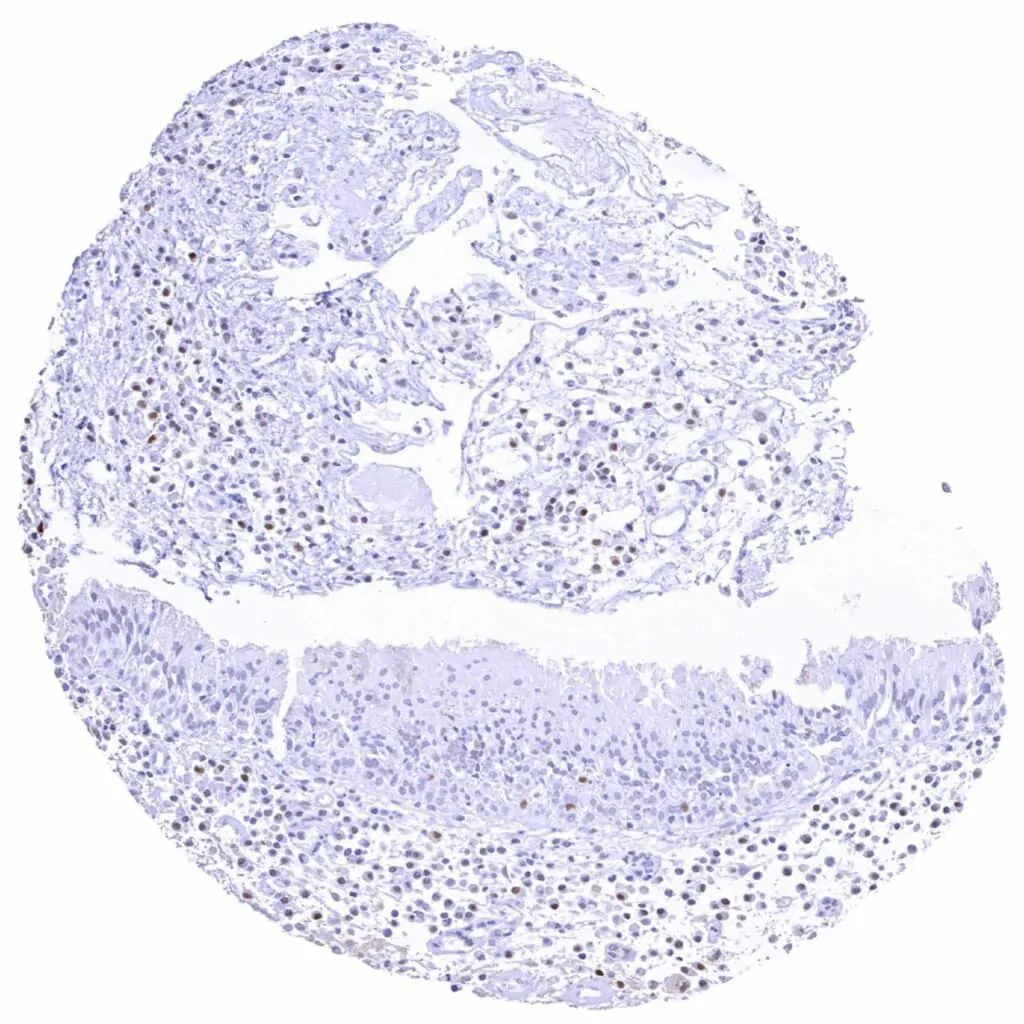

Skin – Weak to strong Cyclin E1 staining of squamous epithelial cells of the upper half of the epidermis. The staining intensity gradually increases towards the surface